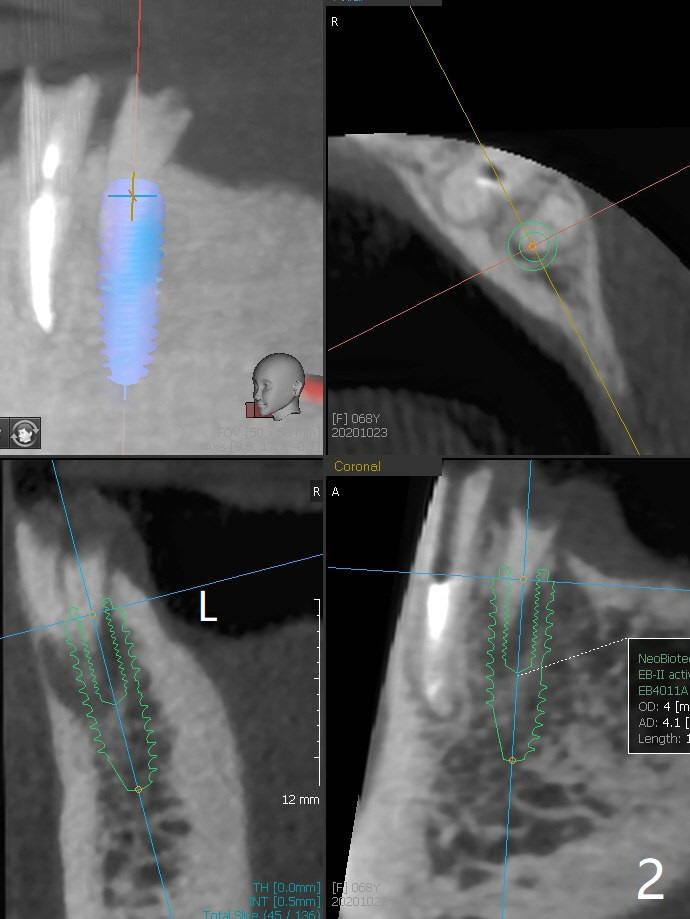

68女五年前戴上上颌全口假牙,下颌局部托牙(由左下3牙冠/桩,右下3,5支撑),最近失去牙冠/桩(图一),终于同意左下4种植 (4x11.5 mm)/球状基台(图二),左下3放置球帽。